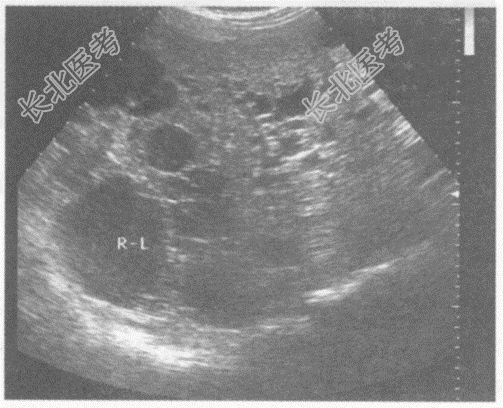

- 单项选择题男性患者,37岁, 自述右上腹隐痛不适。超声综合描述:肝略失常态, 左右叶布满大小不等无回声区,最大位于右叶, 直径5.8cm,内透声不清亮, 包膜完整,后方声加强。超声提示:

A、肝包虫病

B、多囊肝

C、肝多发囊肿

D、肝内胆管扩张

E、肝硬化